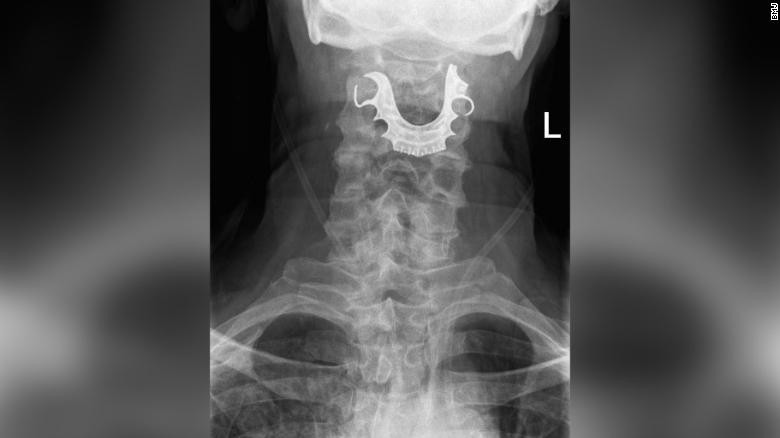

| Đây không phải trường hợp đầu tiên nuốt phải răng giả |

Các chuyên gia cho biết, đây không phải là trường hợp đầu tiên nuốt phải răng giả trong khi bị gây mê: "Không có hướng dẫn nào về cách xử lý răng giả trong quá trình gây mê. Tuy nhiên, nhiều bệnh viện đã cho phép bệnh nhân tháo răng giả ngay trước khi đặt nội khí quản".